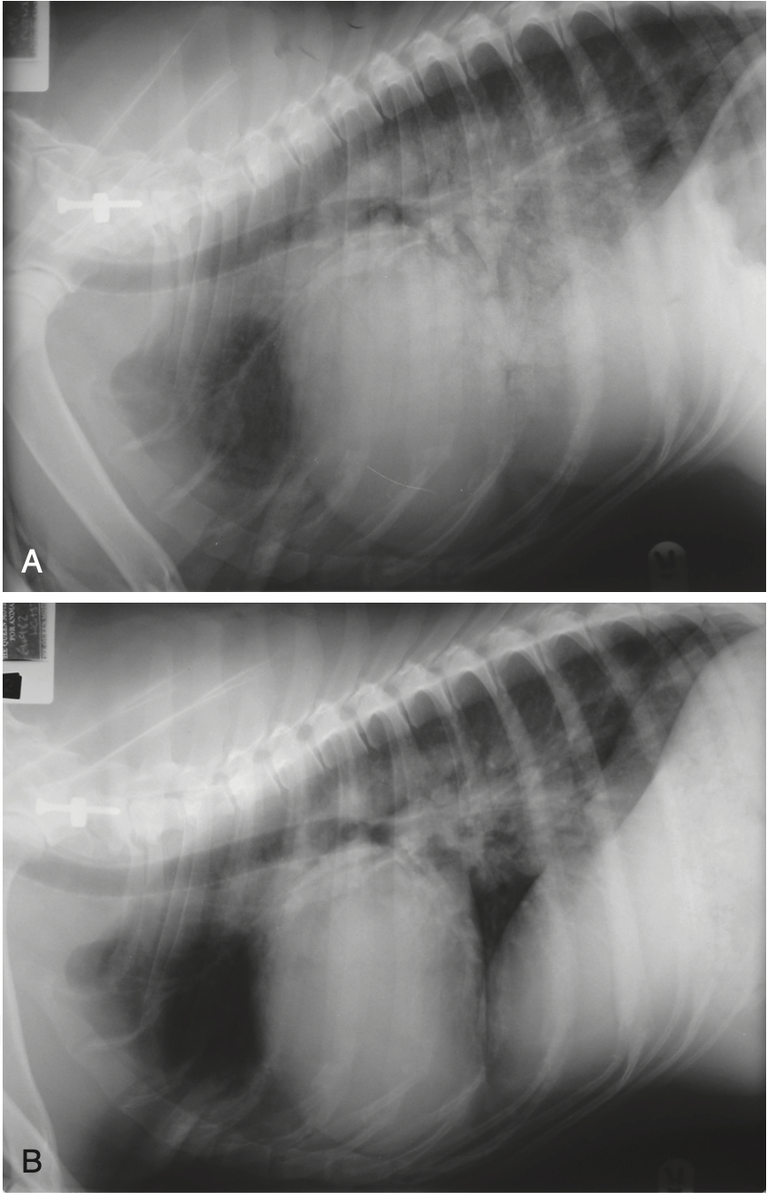

А. Боковая рентгенограмма грудной клетки собаки (доберман), показывающая выраженный отек легких, увеличенный сердечный силуэт и увеличение левого предсердия. У этой собаки была тяжелая застойная сердечная недостаточность, вторичная по отношению к дилатационной кардиомиопатии. B. Боковая рентгенограмма той же собаки через 3 дня после интенсивной диуретической, положительной инотропной и вазодилататорной терапии (фуросемид, добутамин, пимобендан и нитропруссид). Отмечено значительное улучшение альвеолярного рисунка, хотя небольшая отечность все еще присутствуют